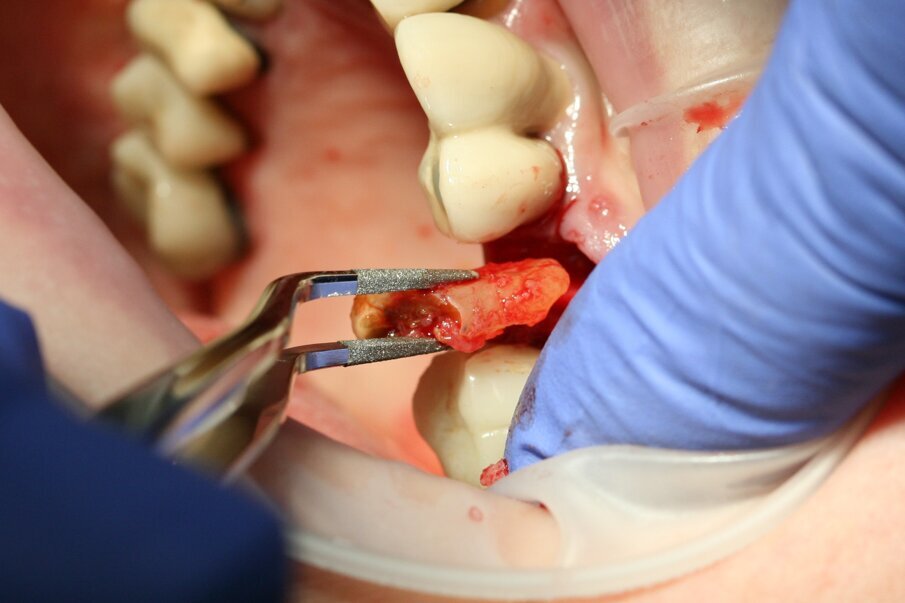

Fig. 8: The root could be lifted out with diamond-coated tweezers.

Luxator P4, with its extremely sharp dual-edge blade, was used at the beginning, followed by Luxator P1 once more space had been created. Although the blades of these sophisticated instruments are reinforced with a titanium coating, they should only be used to cut the periodontal ligament and never to elevate the tooth.